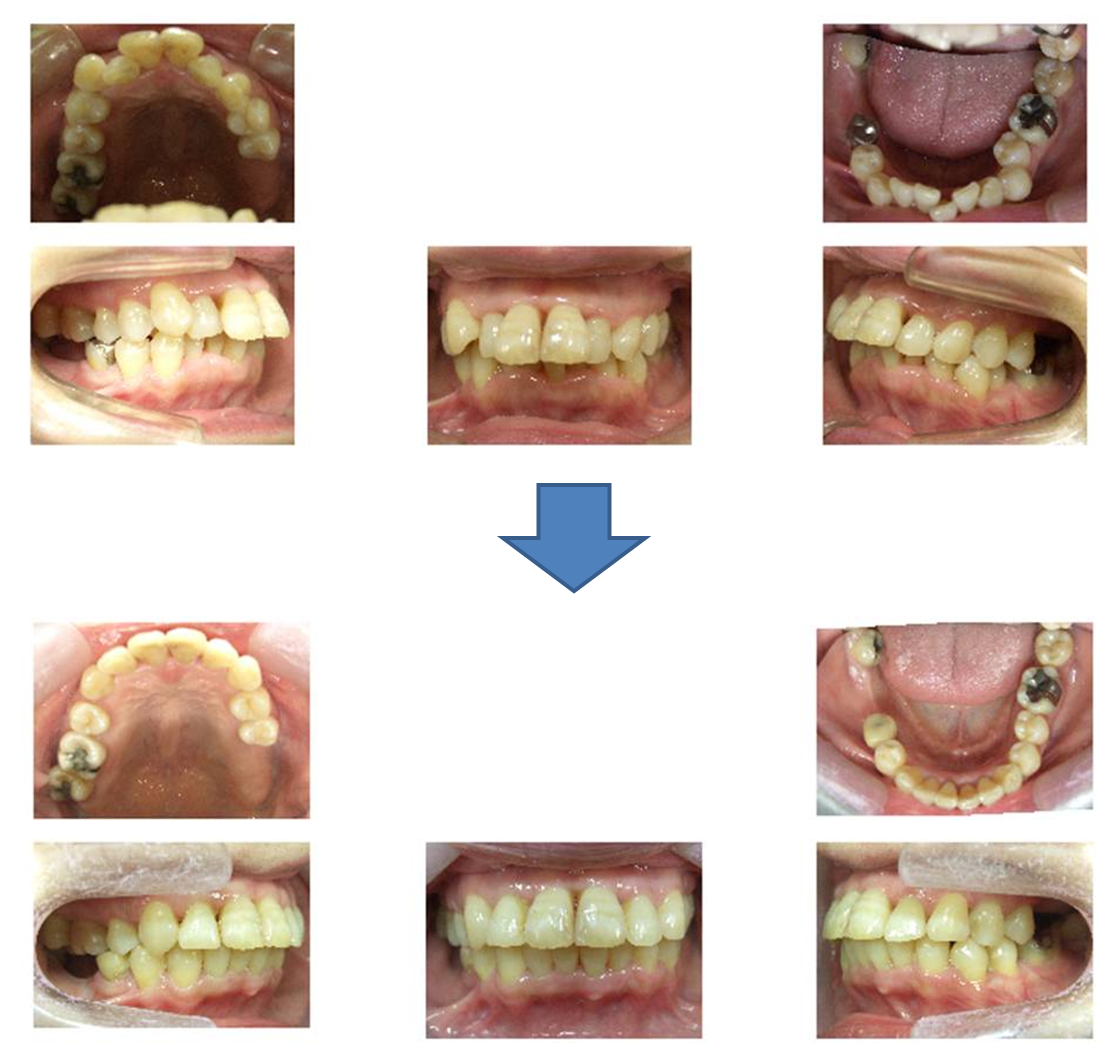

56歳 女性 出っ歯

この症例は、右下と左上の歯がありません。

そして、上下の前歯に前後差があるために前歯でも噛めていません。

という事で、前歯で噛ませることができれば、奥歯がなくとも、入れ歯を入れなくとも、もっと噛めるだろうという事から、矯正治療を行った症例です。

s右上一本歯を抜いて隙間を作り、上の前歯を後ろに下げます。ブラケット装置にて治療。

最初の状態より上の前歯は下がりますが、患者様が想像されているところまで必ずいくとは断言できません。

上の隙間が少し残る事があります。